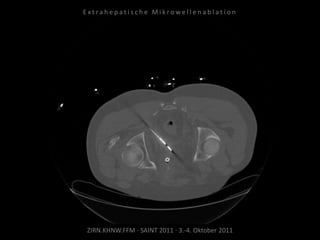

Ablation am 17.08.2010

Metastase lateral der linken Niere:

1 Nadelposition.

Metastase medial des linken

Musculus iliacus: